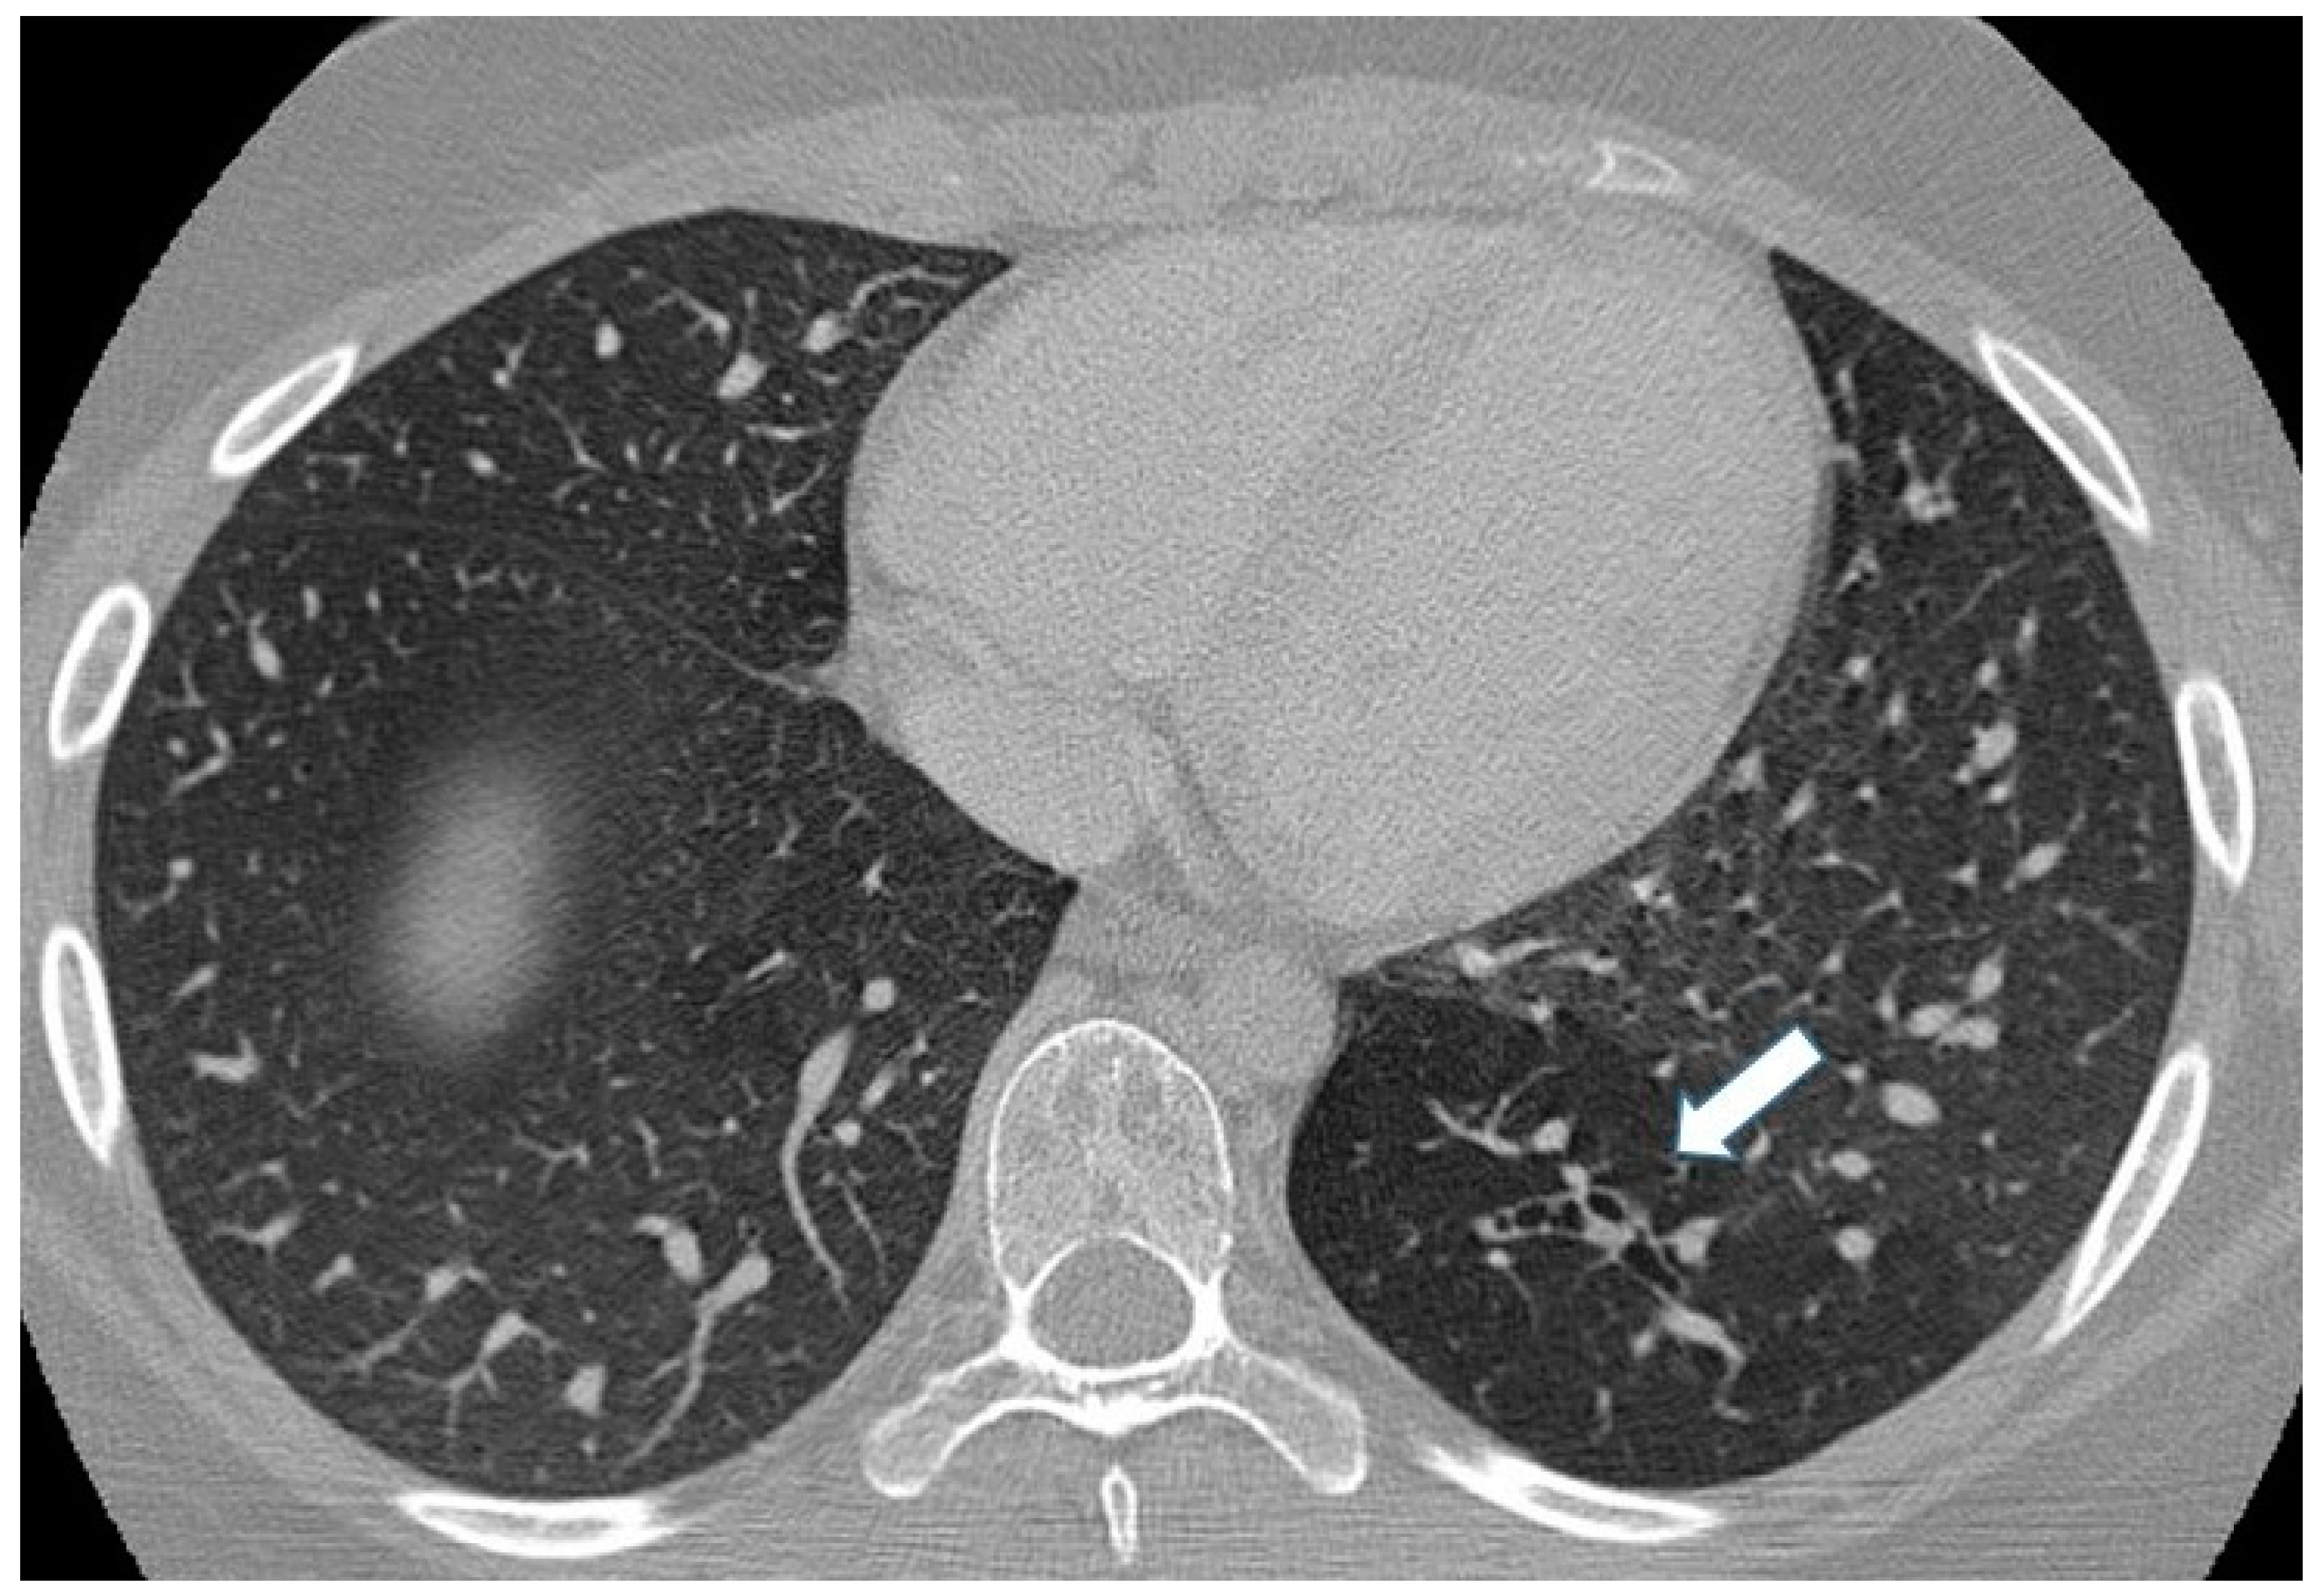

Pulmonary Arteriovenous Malformation